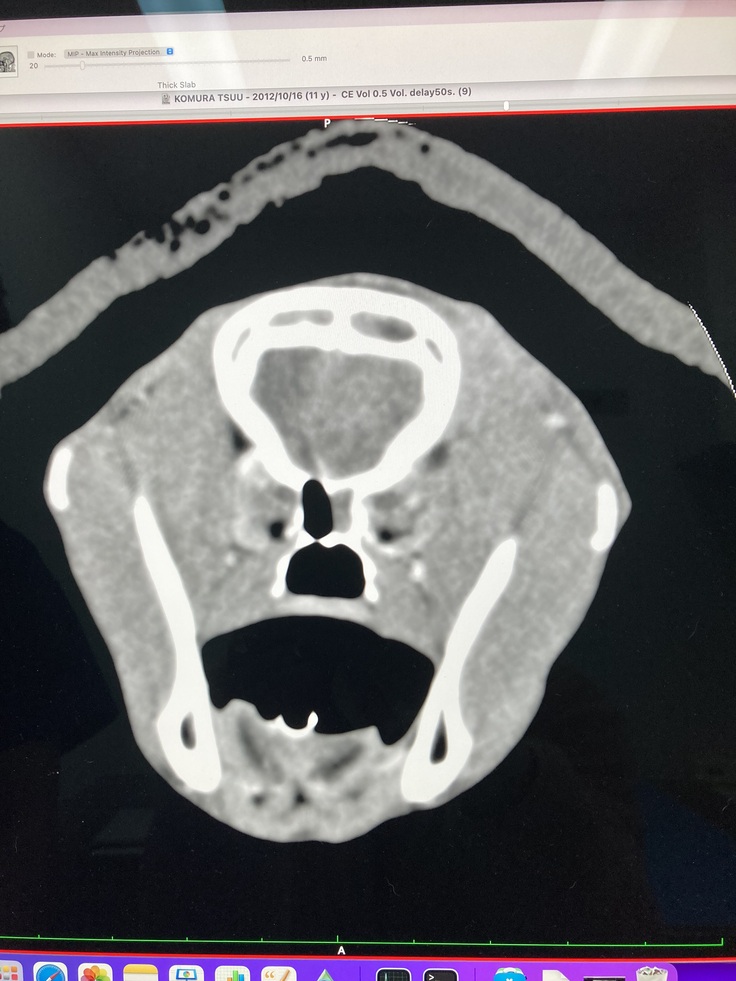

CT画像

←右目 左目→

(画像上側がおでこ辺りになります。左目が腫瘍によって押しつぶされている状態です)

腫瘍によって、脳の形にも変形が見られています

脳みその真ん中の線が大きく左側(右目方向)にズレているのが分かります。